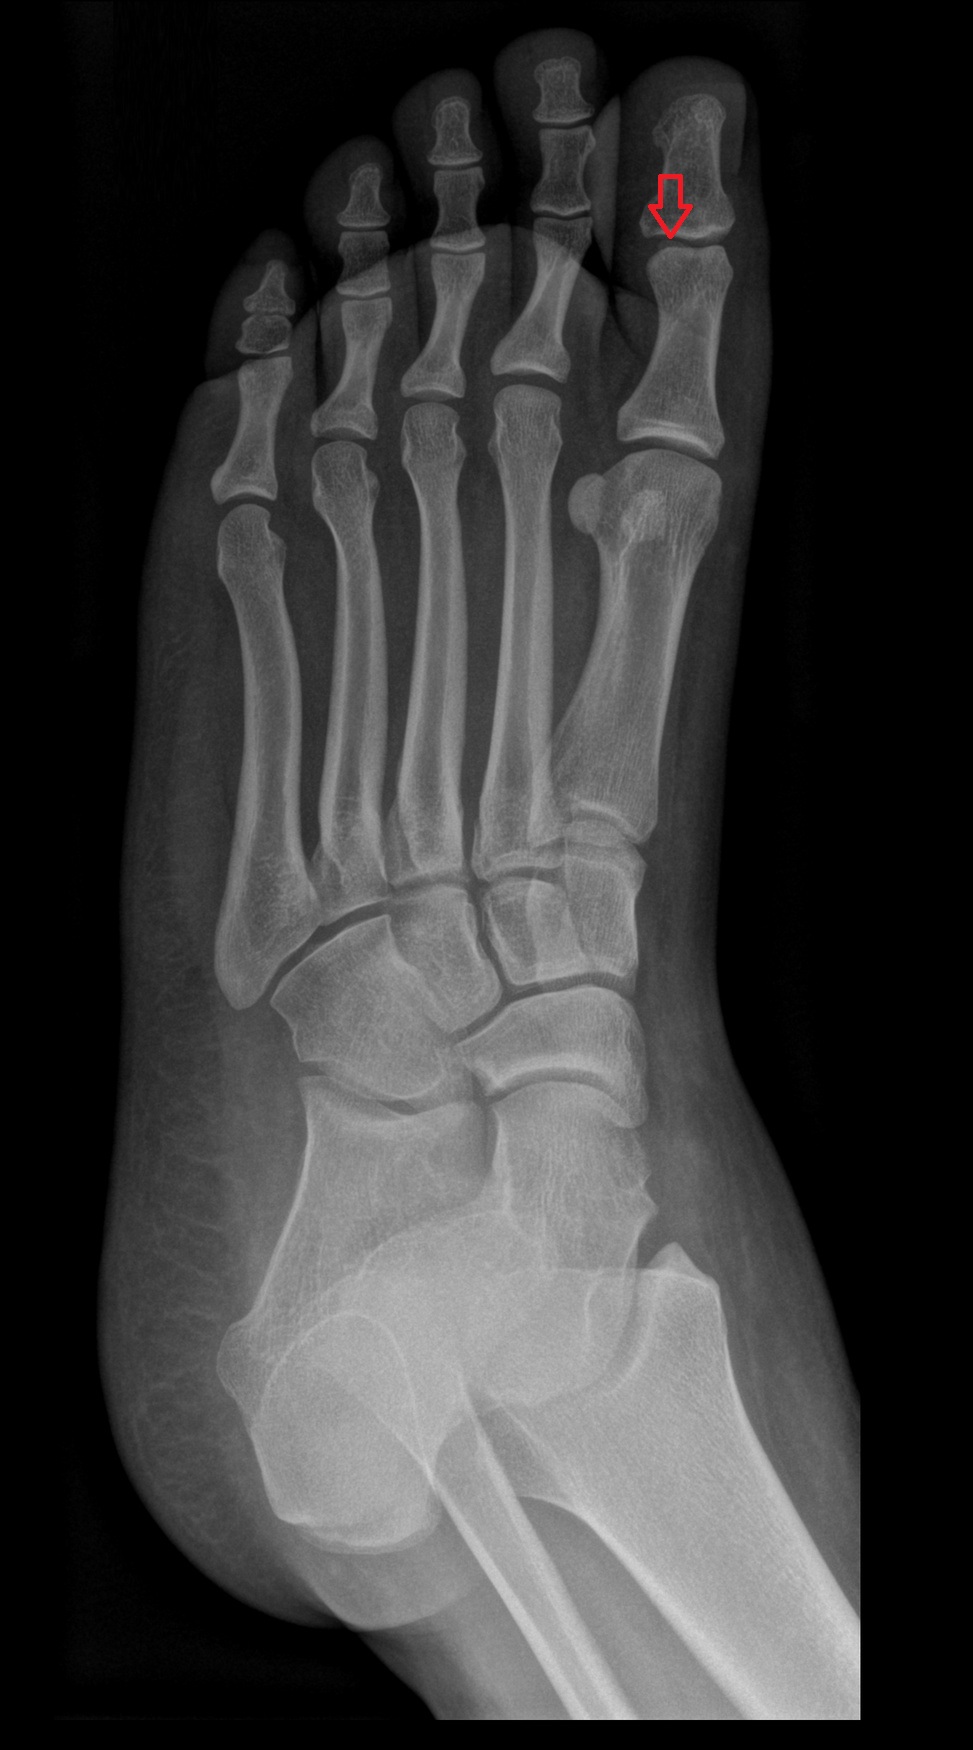

- First metatarsal bone

- Second metatarsal bone

- Third metatarsal bone

- Fourth metatarsal bone

- Fifth metatarsal bone

- Sesamoid bone of great toe

- Lateral sesamoid bone

- Medial sesamoid bone